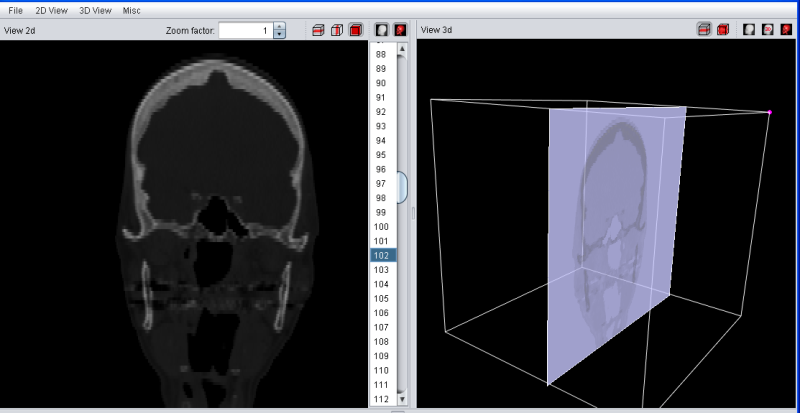

The main window of YaDiV shows two elements to explore and analyse the loaded data: the "View 2d" and the "View 3d". Both will display the raw (volume) data as well as segments and other meta info. The volume data rendering is influenced by the selected Region of Interest (ROI), which can be set at the "Misc" panel in the tool pane below.

After a DICOM Series has been loaded, the "View 2d" will automatically show the selected data. Use the Image Selector to select a slice of interest.

The "View 2d" can show slice images in transversal (default), saggital or frontal mode. Switch between the different modes using the "2d View" menu or with the buttons in the "View 2d" title bar.

After a series has been loaded, the "View 3d" can be used to explore the data.

A first and simple visualization tool is the Slice Plane Mode. It can be activated either via the "3d View" main menu or the button in the "View 3d" title bar. When activated, the "View 3d" will render the plane of the image selected in the "View 2d" at the correct 3D-Position.